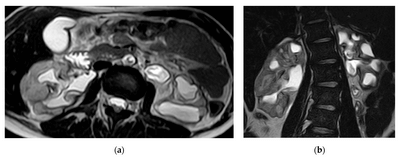

КТ часто використовується для виявлення захворювань нирок, таких як камені в нирках, кісти та пухлини. Зображення, отримані за допомогою КТ, можуть виявити розмір, розташування та форму будь-яких аномальних утворень у нирках. Ця інформація може допомогти лікарям визначити відповідне лікування, наприклад, хірургічне втручання або променеву терапію.